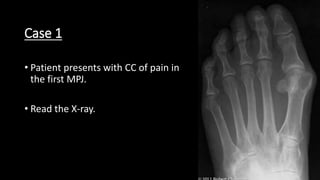

Case 1

• Patient presents with CC of pain in

the first MPJ.

• Read the X-ray.

• This is a Dorsoplantar view of left foot. The hallux abductus (22

degrees) and intermetatarsal (15 degrees) angles are increased.

The hallux interphalangeal angle is normal (5 degrees). The

proximal articular set angle (PASA, 7 degrees) is high normal. The

tibial sesamoid position is 6, and the first metatarsal head medial

eminence is prominent. The proximal and distal articular set axes

cross within the joint.

• Other findings: A geographic decreased density presents in the

medial aspect first metatarsal head and is bounded by a sclerotic

margin. The fourth and fifth toes are in adductovarus position,

and there are contractures at the lesser toe interphalangeal

joints. The primary trabeculations are prominent in the lesser

metatarsal heads.

• Diagnoses: Hallux abductovalgus with bunion deformity.

Subluxation, first metatarsophalangeal joint. Bone cyst. Toe

deformities. Osteoporosis.